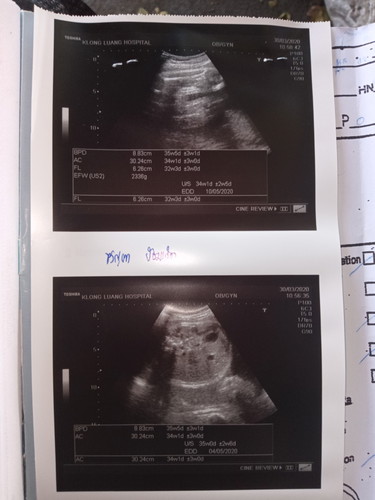

34w2336กรัม

34w2336กรัม น้ำหนักลูกน้อยไปมั้ยค่ะ